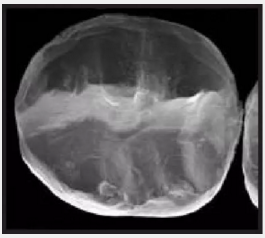

復(fù)合樹脂在即刻充填后,觀察其在電子顯微鏡下的掃描圖像,本次研究選擇了9種具有代表性的復(fù)合樹脂材料。

2.png

IPS Empress Direct Ivoclar Vivadent義獲嘉維瓦登特